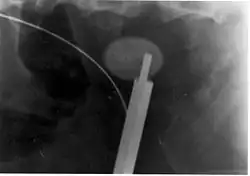

Steinzertrümmerung von innen (intrakorporale Lithotripsie)

Bei der Lithotripsie von innen ist ein endourologisches Verfahren, bei dem ein Endoskop, je nach Lokalisation des Steins entweder über die Harnröhre (retrograde Uroskopie) oder über das Nierenbecken (perkutane antegrade Ureteroskopie) zum Stein geführt wird. Der französische Chirurg Jean Civiale entwickelte schon in den 1820er Jahren ein Gerät zur mechanischen Zerkleinerung von Blasensteinen, welches über die Harnröhre in die Harnblase eingeführt werden konnte. 1983 konnten Huffman und Mitarbeiter erstmals einen Stein mittels Ultraschall zertrümmern, 1990 kam erstmals ein pneumatischer Lithotripter und 1995 erstmals ein Holmium-Yttrium-Aluminium-Granat-Festkörperlaser (Ho:YAG-Laser) zur Uretersteinzertrümmerung zum Einsatz.[6]